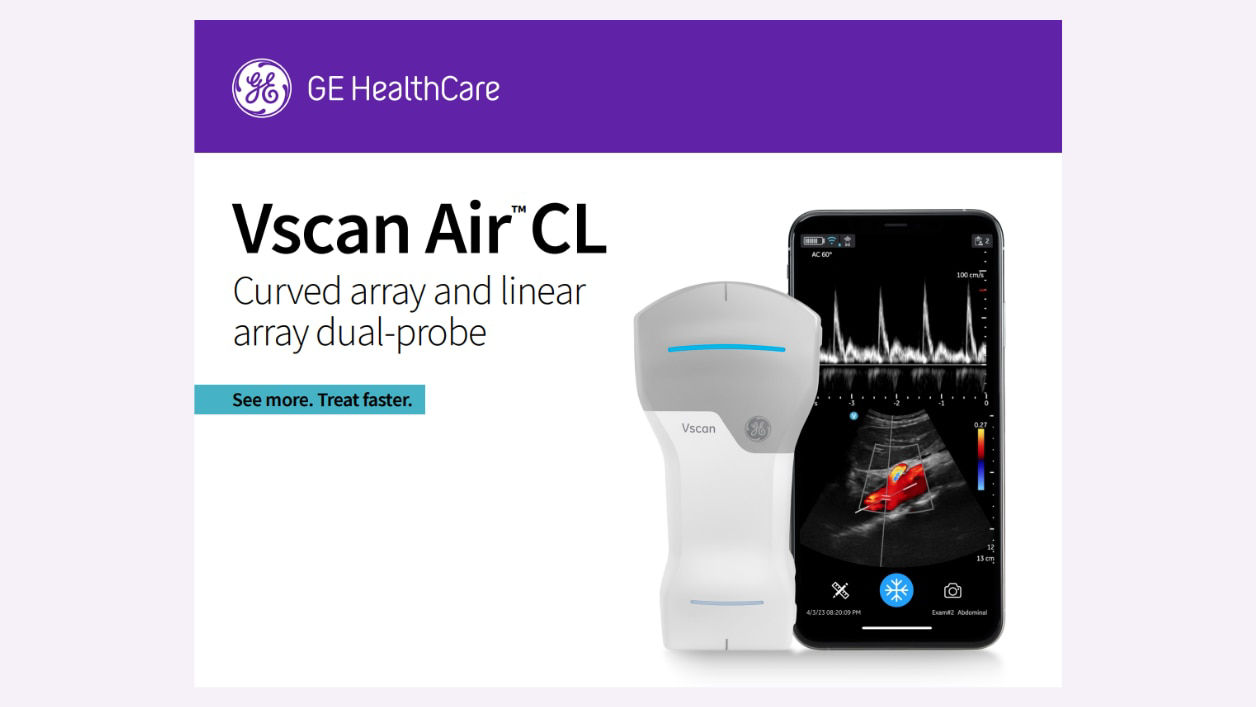

AI supported

Available AI features assist in clinical image interpretation and can help enhance diagnostic accuracy.

Immediate assessments

Immediate imaging can lead to faster treatment decisions, improving patient outcomes.

Enhanced mobility

Ultra portable and can be used in various critical care settings.

Reduced time

Handheld ultrasound can help reduce the time between diagnosis and treatment.